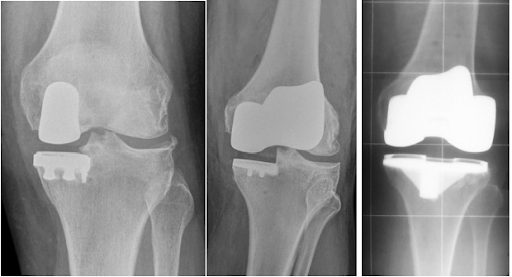

Total Knee Replacement (TKR) has been around for a few decades. It has improved the lives of many patients crippled with disabling arthritis. However, like any technological advancement, it is not without its drawbacks. Traditionally, it has been taught that joint replacement should be performed as a last resort, in patients over 60 years of age and are sedentary in nature.

Options to TKR include unicondylar or bicompartment knee replacement. It is possible now to replace a specific compartment of the knee, rather than the entire knee. This procedure can be viewed as a “pre-TKR surgery”. With cruciate preservation and less surgery, recovery is faster. However, patients qualifying for these implants are not common, as they need to be treated earlier rather than wait for all compartments to be involved.

In summary, TKR has undergone a sea-change over the past 5 years. Hip and Knee surgeons now have a wider armamentarium to tackle knee arthritis and provide a longer lasting implant.